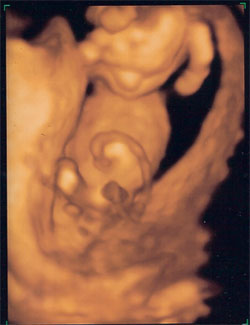

4D Genezis 15 hét 4 naposan

Kép Itt alszik a kisfiam

Kép Puszit kűld

Kép